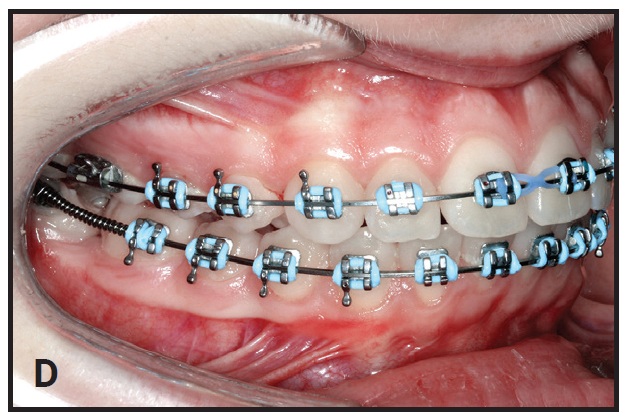

The second molar quickly uprights in one or two appointments (D). Note that a long cinch should always be placed at the end of the archwire (E).